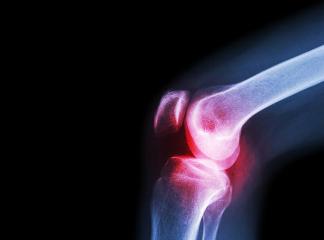

Остеоартрит (ОА) также известен как дегенеративное заболевание суставов. Это состояние, при котором хрящ, ткань, которая защищает конец каждой кости в суставе, стирается, и кости начинают тереться. Это может вызвать боль, отек и плохую подвижность сустава.

С ухудшением состояния кости теряют форму. Могут возникнуть наросты, называемые костные шпоры. Кроме того, и кости, и хрящи могут отрываться и плавать в полости сустава. Это может вызвать воспалительный процесс, что усугубляет боль, а также повреждения хрящей и костей.